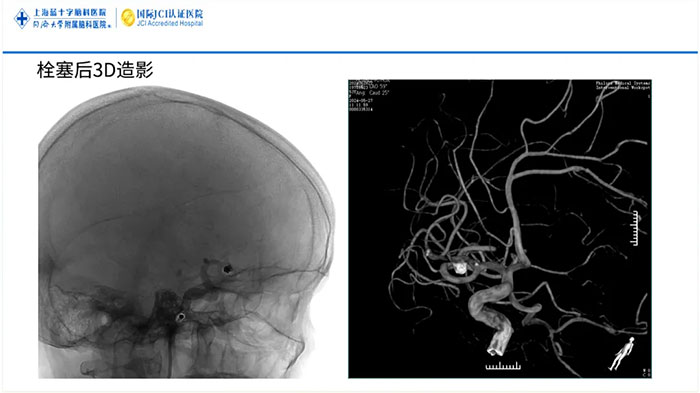

常规的介入手术治疗脑血管狭窄需要在术中进行多次交换,如导丝交换、球囊交换以及支架微导管交换,手术步骤相对较多,手术风险也相对增加。而“零交换”技术,通过使用新材料输送型球囊扩张导管,可以免去手术步骤中的导丝交换、球囊交换以及支架微导管交换步骤,在球囊扩张后直接释放支架,简化操作步骤,提高手术的安全性,缩短手术时间,为患者带来了福音。

上海蓝十字脑科医院脑血管病科神经介入团队已开展了十余例“零交换”技术治疗颅内动脉粥样硬化性狭窄的手术,涉及大脑中动脉、大脑前动脉、大脑后动脉、基底动脉、颈内动脉颅内段、椎动脉V4段等颅内动脉部位,均为高难度四级神经介入手术。